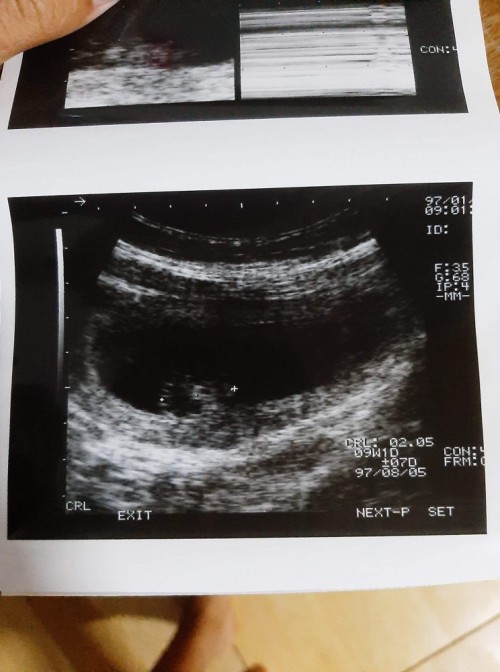

อันนี้ตอน9วีค1วันคะ เห็นตัวน้อง เห็นหัวใจกะพริบ แต่น้องยังเล็กมากคะ ขนาดแค่2เซน